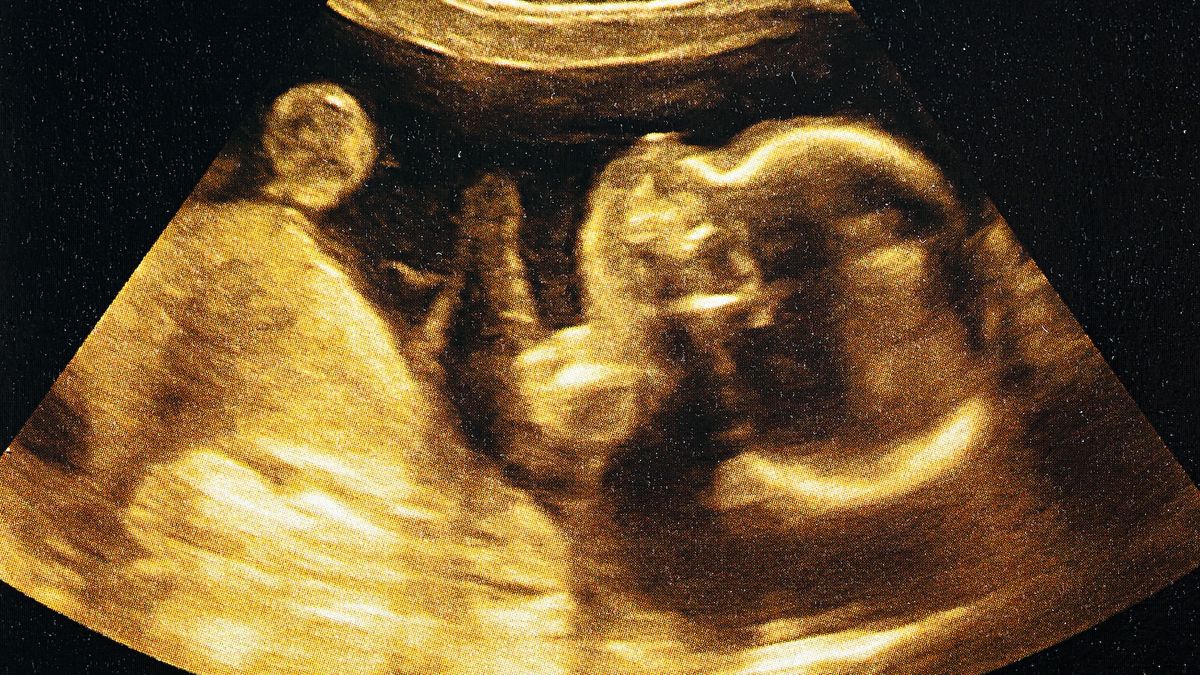

The infant involved in the recent case was found to be at risk for SMA type 1 after undergoing genetic testing in the womb. The parents had already had one child with confirmed SMA type 1 who had previously passed away. The tests revealed that the growing fetus also had mutations in the SMN1 genes on both chromosomes.

At 32 weeks of pregnancy, the mother started taking risdiplam daily for six weeks. Testing at the time of birth indicated that the drug had indeed been entering the baby’s system while in the womb. Roughly one week after birth, the baby herself was given the drug orally.